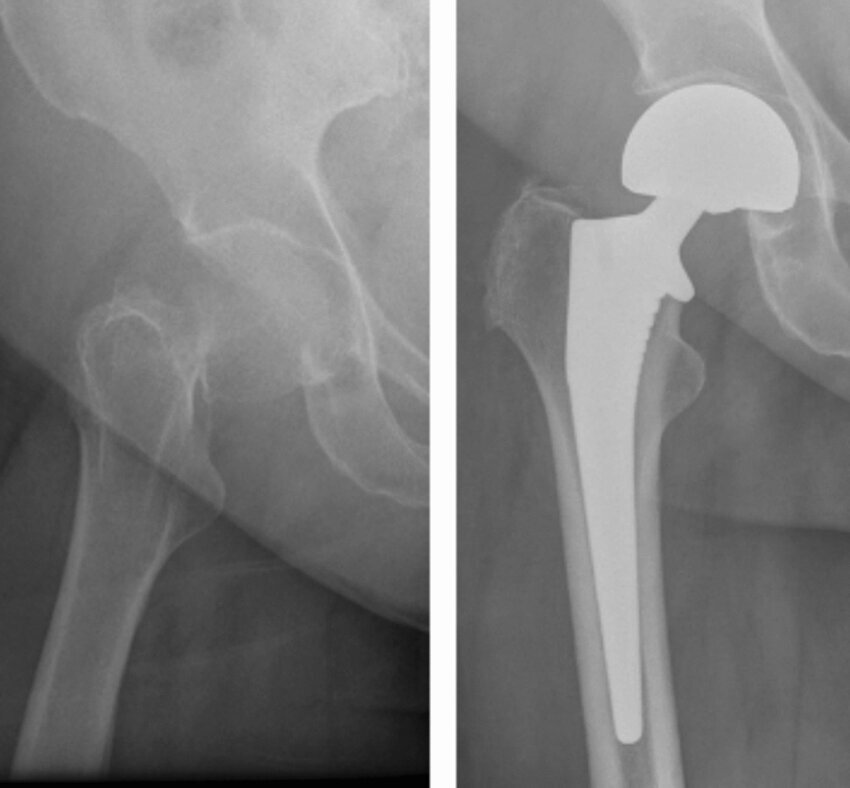

Registry data corroborate these findings with the Swedish registry PROMs consistently reporting higher satisfaction and functional scores after THA compared with HA.20 Conversion of HA to THA for acetabular erosion restores function but carries higher revision and complication rates than primary THA.75 (Figure 3)

Patients with inflammatory arthritis or immunosuppression